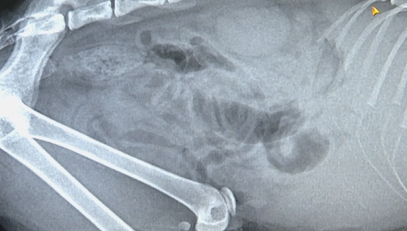

东方动物医院 负责人 王先生:这个是操作保定的正常手段,现在余女士质疑我们压得过紧包得过严,导致它的死亡,但是它的死亡我们也拍了片,也给余女士做了解释,她的猫咪是有胸水 ,是因为胸腔积液导致她猫咪死亡。

余女士:在抽血的过程中猫咪已经死亡了,而他们所谓的拍片已经是等到猫咪死亡两个小时以后才拍的,反咬我一口说是我家猫咪有病病死的。这样避而不见的态度,不管是拿起法律的武器保护自己,只要有一点点小小的希望,我都会全力以赴的去争取。